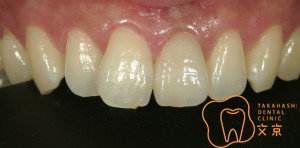

■前歯を治したい。 オールセラミックスによる審美治療

■前歯を治したい。40代男性 オールセラミックスによる審美治療

■前歯を治したい 精密審美治療・セラミックス治療

■前歯 精密審美治療

■前歯のセラミックス治療 審美治療

■前歯のオールセラミックス治療

■保険の前歯を直したい